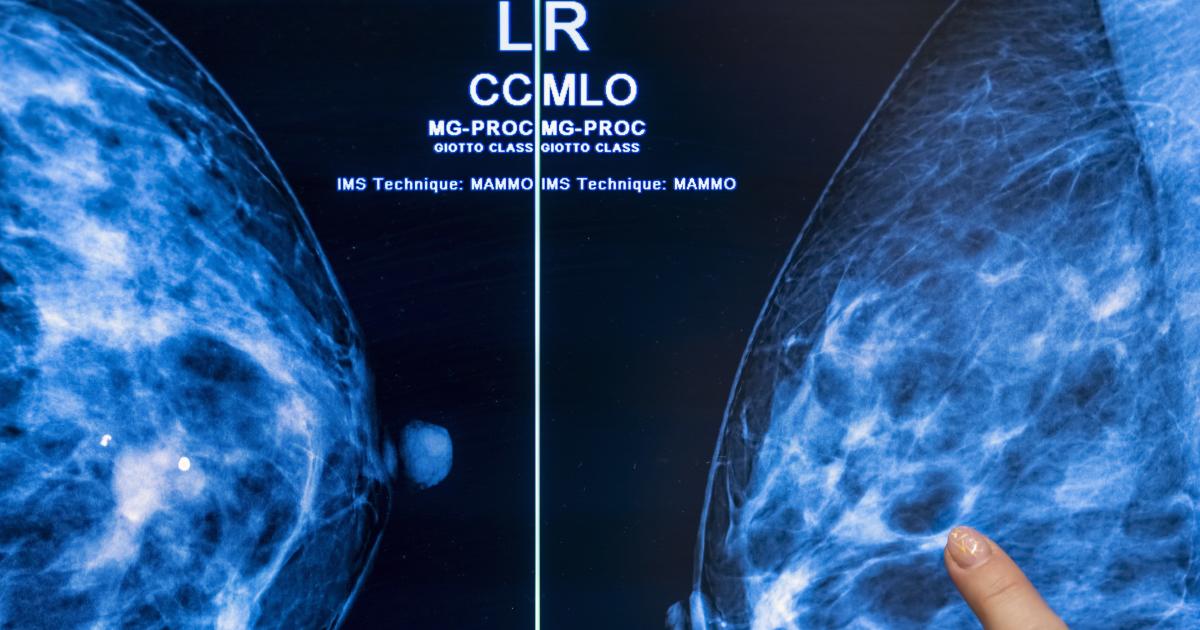

Ο προσυμπτωματικός έλεγχος καρκίνου με τη βοήθεια τεχνητής νοημοσύνης θα μπορούσε να μειώσει τον φόρτο εργασίας των ακτινολόγων στο μισό

διαπίστωσε ότι η χρήση της τεχνητής νοημοσύνης στον προσυμπτωματικό έλεγχο καρκίνου με μαστογραφία μπορεί να μειώσει με ασφάλεια τον φόρτο εργασίας του ακτινολόγου σχεδόν στο μισό χωρίς τον κίνδυνο αύξησης των ψευδώς θετικών αποτελεσμάτων. Στην πραγματικότητα, η μελέτη διαπίστωσε ότι οι συστάσεις του AI ήταν

«Ο έλεγχος μαστογραφίας που υποστηρίζεται από AI οδήγησε σε παρόμοιο ποσοστό ανίχνευσης καρκίνου σε σύγκριση με την τυπική διπλή ανάγνωση, με σημαντικά χαμηλότερο φόρτο εργασίας ανάγνωσης οθόνης, γεγονός που δείχνει ότι η χρήση της τεχνητής νοημοσύνης στον έλεγχο μαστογραφίας είναι ασφαλής», διαπίστωσε η μελέτη.

Η μελέτη διεξήχθη από μια ερευνητική ομάδα από το Πανεπιστήμιο Lund στη Σουηδία και, κατά συνέπεια, παρακολούθησε 80.033 Σουηδές (μέση ηλικία 54 ετών) για λίγο περισσότερο από ένα χρόνο το 2021-2022. Από τους 39.996 ασθενείς στους οποίους ανατέθηκαν τυχαία προληπτικοί έλεγχοι καρκίνου του μαστού με τεχνητή νοημοσύνη, το 28 τοις εκατό ή 244 τεστ επέστρεψαν καρκίνους που ανιχνεύθηκαν με έλεγχο. Από τους άλλους 40.024 ασθενείς που υποβλήθηκαν σε συμβατικές εξετάσεις καρκίνου, μόλις το 25 τοις εκατό, ή 203 τεστ, επέστρεψαν καρκίνους που ανιχνεύθηκαν από τον έλεγχο.

Από αυτούς τους επιπλέον 41 καρκίνους που εντοπίστηκαν από την πλευρά της τεχνητής νοημοσύνης, οι 19 αποδείχθηκαν διεισδυτικοί. Τόσο οι προβολές με τεχνητή νοημοσύνη όσο και οι συμβατικές προβολές είχαν ποσοστό ψευδώς θετικών 1,5%. Το πιο εντυπωσιακό είναι ότι οι ακτινολόγοι από την πλευρά της τεχνητής νοημοσύνης έπρεπε να εξετάσουν 36.886 λιγότερες μετρήσεις οθόνης από τους ομολόγους τους, μείωση 44 τοις εκατό στον φόρτο εργασίας τους.

«Αυτά τα πολλά υποσχόμενα ενδιάμεσα αποτελέσματα ασφάλειας θα πρέπει να χρησιμοποιηθούν για την ενημέρωση νέων δοκιμών και αξιολογήσεων βάσει προγραμμάτων για την αντιμετώπιση της έντονης έλλειψης ακτινολόγων σε πολλές χώρες, αλλά δεν αρκούν από μόνα τους για να επιβεβαιώσουν ότι η τεχνητή νοημοσύνη είναι έτοιμη να εφαρμοστεί στον μαστογραφικό έλεγχο». Η επικεφαλής συγγραφέας, Dr Kristina Lång, προειδοποίησε σε μια ανακοίνωση: «Πρέπει ακόμη να κατανοήσουμε τις επιπτώσεις στα αποτελέσματα των ασθενών, ειδικά εάν ο συνδυασμός της τεχνογνωσίας των ακτινολόγων με την τεχνητή νοημοσύνη μπορεί να βοηθήσει στην ανίχνευση καρκίνων μεσοδιαστήματος που συχνά χάνονται από τον παραδοσιακό έλεγχο, καθώς και οικονομική αποδοτικότητα της τεχνολογίας».